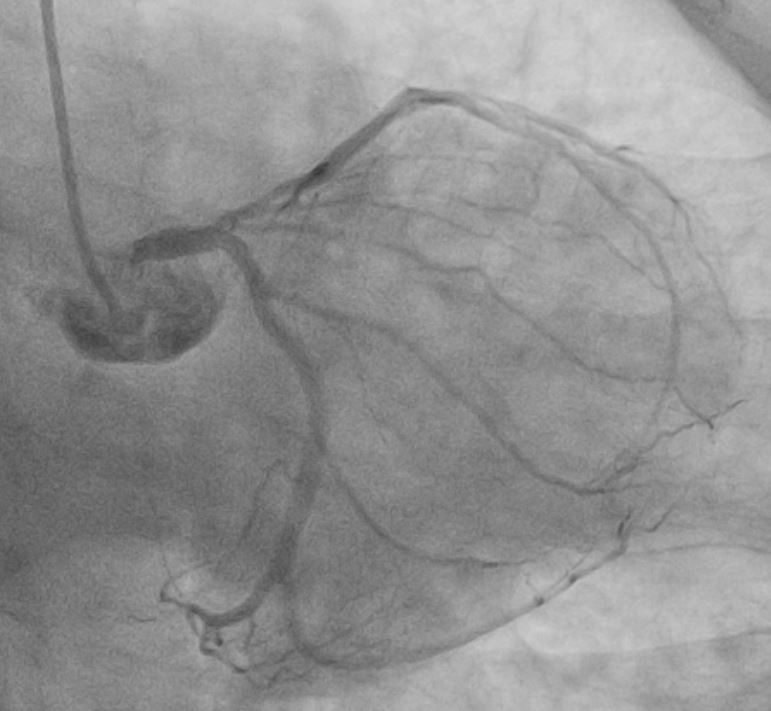

Coronary angiogram shows severe disease ostio-proximal LAD with severe calcification/calcium nodule , mild disease left circumflexsevere stenosis proximal and mid RCA -recessive

Right Radial approach, Slender 6/7Fr , EBU 3.5 7FR changedto EBU 3.0 7FR Sion blue to LCX, Run-through floppy to LAD IVUS run to LAD Fibro calcified lesion ostial LAD - calcium arc 180 degrees with calcium nodule, ostial LAD 3.48mm2 , tightest proximal LAD 2.31mm2 distallumen size 3.0mm and proximal 3.5mm and ostial 4.0mm ostial LM MLA 10.8mm Used microcatheter fine cross to LAD , Exchange with balloon trapping withRotaWireRotablator 1.5burr introduced- 2 runs high speed 180kph and2 runs at 80kph IVUS done post Rotablator - tightest proximal LAD 2.31mm2 -->3.22mm2 , ostial LAD 3.48mm2 -->4.51mm2 Predilate further NC 3.5x15mm up to 16atm Stented Synergy monorail 3.0x32mm body LM to proximal LAD at11atm with guide plus 6FRpost dilated NC 3.5x12mm up to 20atm Guiding catheter slipped out and lost the system, tried to reengage but challenging thus decided to change to right femoral puncture to use EBU3.5/7fr ,post dilate LM-LAD NC 4.0/12mm 6atmOstial LCX pinched - decided for Kissing balloon inflation and DCB LCX ostium predilated Ostial LCX 2.75x15mm up to 8atm Kissing inflation performed with NC emerge 3.5X15mm LAD, NC2.75x12mm in LCX 8atm DCB AGENT MONORAIL 2.75X15 MM 8atm 60seconds to ostial LCX last POT with NC 4.0x12mm up to 16atm IVUS done stent well opposed, Ostial LAD MSA 8.25mm2Proximal MSA 5.64mm2 TIMI III flow

In summary, this was a complex PCI for a severely fibro-calcified ostial and proximal LAD lesion with significant calcium arc and a calcium nodule confirmed on IVUS. Despite initial right radial access with a Slender 6/7 Fr system, guide support with EBU 3.5 and later EBU 3.0 remained suboptimal, ultimately necessitating conversion to a right femoral 7 Fr approach for adequate support. Overall, the case highlights the importance of adaptive access strategy, aggressive plaque modification, IVUS-guided optimization, and bifurcation management to achieve an excellent final physiological and angiographic result in a heavily calcified LM–LAD lesion.